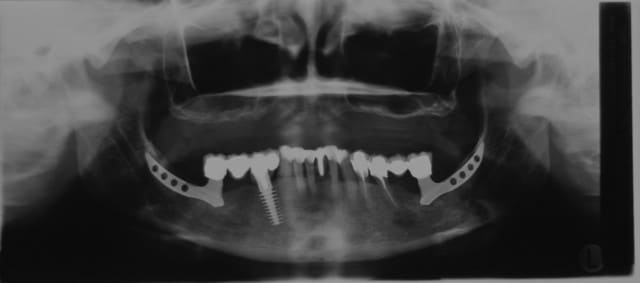

heu ... la y a plus beaucoup d'os

> T'as pas dû regarder la mandibule mon gars. C'est elle le vrai blème...

La pano du premier post...

oui mais là les solutions existent aussi:

de 2 à 5 implants

ou 4/5 +2

ou divers trucs bizarre, déplacement du V (pas utile je pense) lames ramique +implants antérieurs etc...

Tu sais, pxav, la basale est bien plus normée que ces drôles de cadres ramiques ou autres implants ramiques...

Alors c est rigolo de voir cette pano de cadre ramique que certains trouvent presque normale alors que qd les praticiens voient des cas de basale ils nous sautent à la gorge sans réfléchir et presque comme si c était un réflexe conditionné

y a plus beaucoup d'os